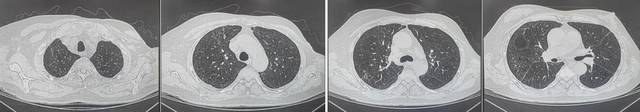

患者2月后门诊复查CT

经重症医学科全体医护人员精心治疗与护理,患者各器官功能逐步恢复,氧合情况显著改善。9日后成功脱机拔管,复查胸部CT显示双肺渗出明显吸收;两个月后门诊复查CT显示,肺功能进一步好转,患者及家属倍感欣慰。